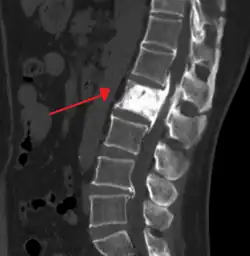

An ivory vertebra due to probable Paget disease